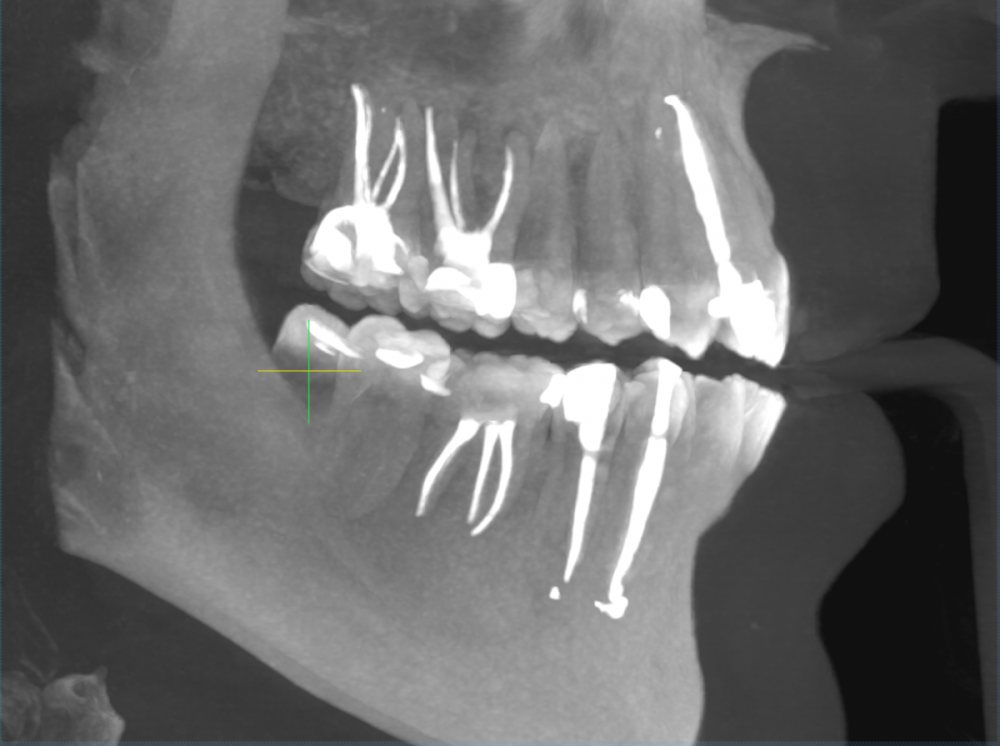

sewif Опубликовано 5 июня, 2020 Автор Поделиться Опубликовано 5 июня, 2020 (изменено) ЗдравствуйтеСегодня сделал контрольное КТ. После лечения прошло где-то 5-5,5 месяцев. КТ делал в одной клинике, а доктор который лечит зубы работает в другой клинике (к нему визит послезавтра) . В клинике в которой делал КТ, работает ЧЛХ из Моники, я к нему сразу на консультацию и записался. Мнение хирурга:1) По верхней кисте заметная положительная динамика.2) По нижней кисте: непонятно. Далее пишу сумбурно, в голове каша но как я понял: похоже на то, что жидкость из кисты ушла. Киста "скукожилась" и что-то в ней образовалось (непонятно что..фиброз? или что-то другое). Также сказала, чтобы врач внимательно посмотрел 5 зуб...возможно его стоит тоже депульпировать.Вердикт: ждать еще 3 месяца. Также сказала, что если бы она не видела снимок от октября 2019г...то по текущему снимку, сказала бы что у меня не кисты, а другие болячки с зубами....по нижней амеоба-чего-то там Первый снимок от 24 октября 2019Второй снимок от 05 июня 2020 Изменено 5 июня, 2020 пользователем sewif Ссылка на комментарий

Irouil Опубликовано 5 июня, 2020 Поделиться Опубликовано 5 июня, 2020 Есть положительная динамика и наверху, и внизу Ссылка на комментарий

Bier Опубликовано 5 июня, 2020 Поделиться Опубликовано 5 июня, 2020 на мой взгляд явное улучшение и вверху и внизу Ссылка на комментарий

sewif Опубликовано 23 мая, 2021 Автор Поделиться Опубликовано 23 мая, 2021 Здравствуйте Сегодня сделал снимок. Прошу почти год с предыдущего снимка. В этот раз делал снимок как сказал доктор - в Пикассо. Программа непонятная и может скриншоты не очень, если нужно как-то иначе то прошу сообщить. Я не вижу кисты, ее нет или я не так смотрел? Ссылка на комментарий

Irouil Опубликовано 23 мая, 2021 Поделиться Опубликовано 23 мая, 2021 Эти картинки не особо показательны, конечно, но очевидно, что от изначальной ситуации тут не осталось примерно ничего 1 Ссылка на комментарий